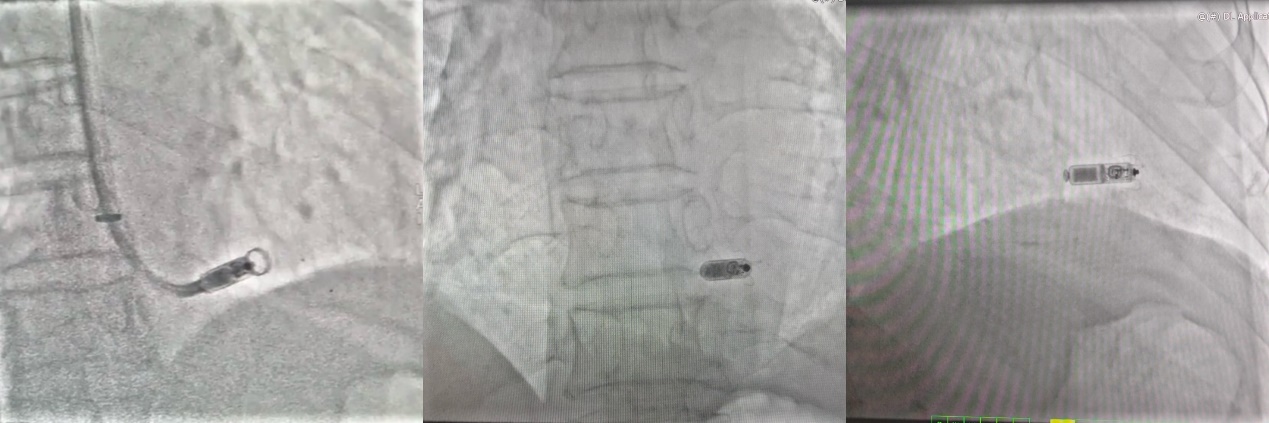

7月6日下午,经超声引导下颈内静脉穿刺成功后,手术正式开始。由于颈内静脉更直,送入递送系统过程中有系统头端压力过大的风险。为避免此风险,需在术中全程X线透视并保持递送系统处于弯曲状态,采用多角度X线透视以确保起搏器始终处于间隔位置。顺利进入27Fr的传送鞘管后起搏器于间隔部位释放成功,参数满意。

由于经颈内静脉途径做牵拉试验时,固定翼的活动度不易观察,手术团队也在多角度多体位反复确认后得以通过牵拉试验。手术用时仅30分钟,术后第一天患者下地活动,穿刺部位加压包扎4—6小时后改为普通包扎,程控提示起搏器起搏与感知功能良好。